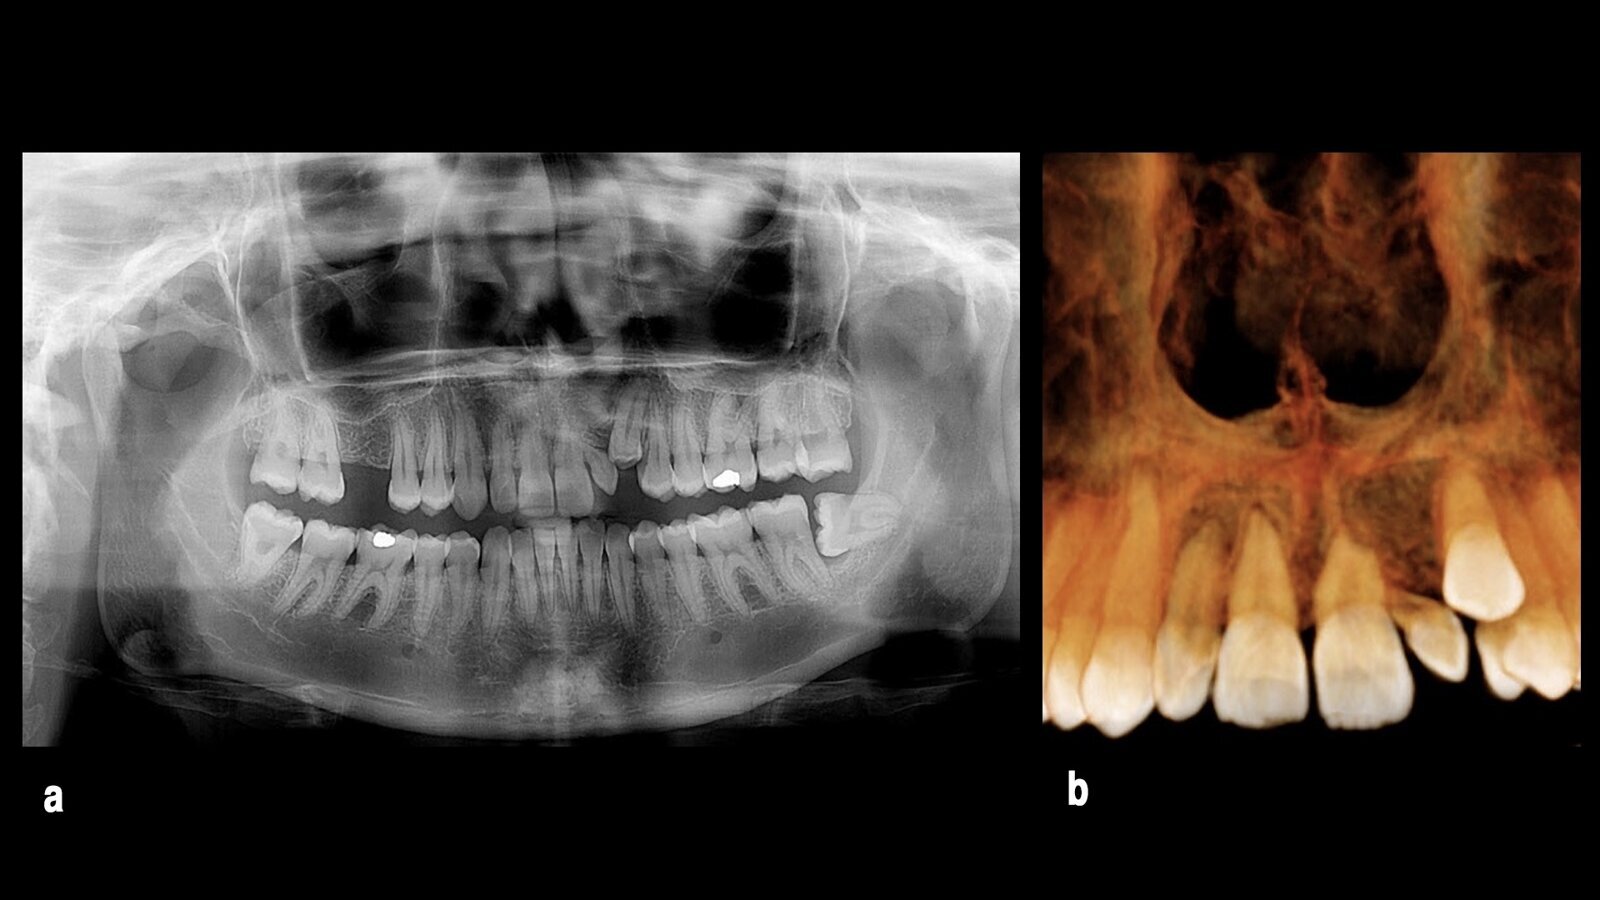

Los dientes con acortamiento radicular pueden ser sometidos a terapia de ortodoncia teniendo en cuenta indicaciones y precauciones precisas, así como realizando un control radiográfico de los mismos para su evaluación durante el tratamiento. En las radiografías de control ya se puede observar una mejoría en el paralelismo radicular (Fig. 6).

Figura 6. Los dientes con acortamiento radicular pueden ser tratados efectivamente (a), como demuestra el control radiográfico de progreso del tratamiento (b).